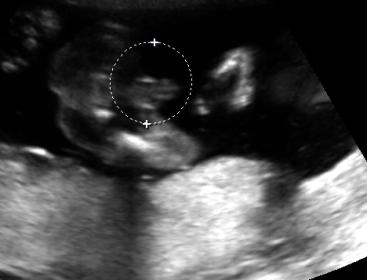

I stupidly went on ingender's site and looked at their ultrasound opposites thread and now I'm not so sure this is really a girl. The one picture looks like it's taken from too far back and could be scrotum and the other one looks like a girl, but I'm not so sure. I have an ultrasound at 24 weeks and 28 weeks so I'll be having the tech double check each time, but right now I'm having doubts! Are these ultrasound pictures good shots of a girl? She was able to tell me right away what the gender was so she didn't really look around too much (even though I did make her double check 3 times...)

Attachment 29402